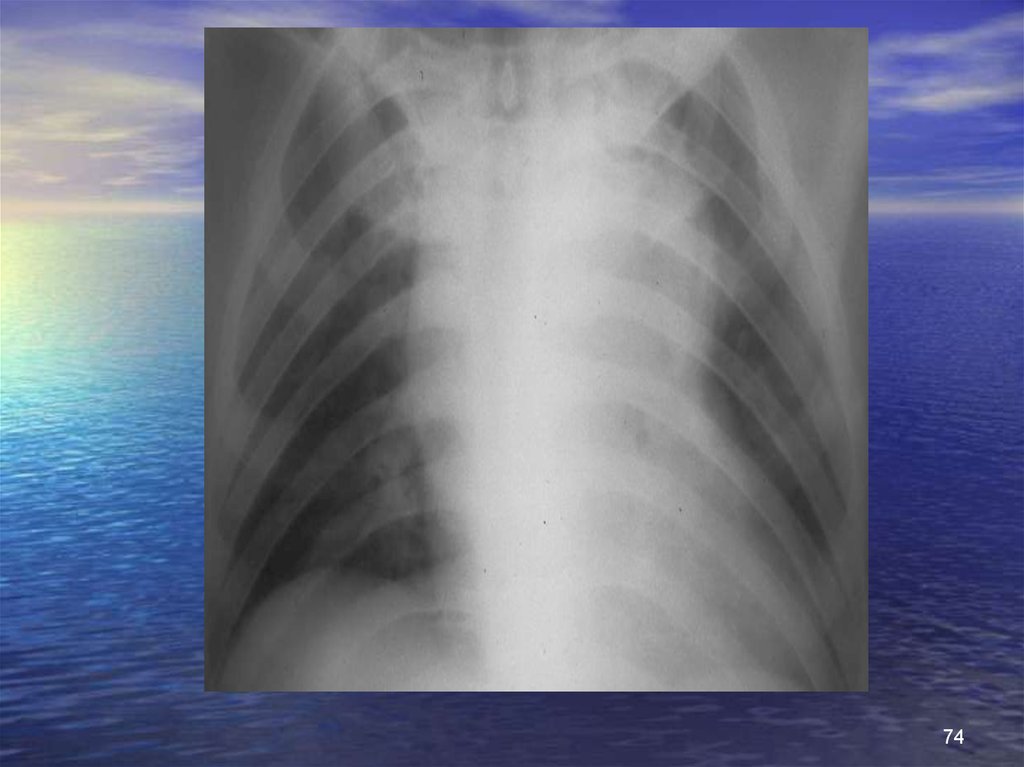

74.

74